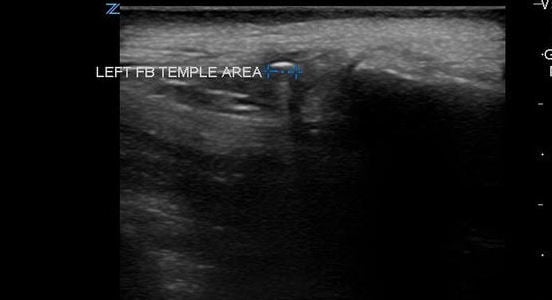

- The area is scanned throughout its entirety in search for a hyperechoic object in both the sagittal and transverse planes as it can sometimes be much easier to visualize an object in one plane but not the other. Be aware of possible surrounding tissue inflammation or abscess.

- Visualization of foreign bodies is easiest when the probe is parallel to the object and therefore attempts should be made to visualize the area in question from many angles if possible.

- Once a foreign body is localized, the depth from the skin can be measured as well as the size of the object.